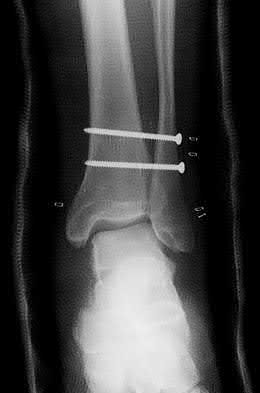

4. # After undergoing the treatment seen in Figure A, when should a patient be expected to safely operate the brakes of an automobile?

Corrent answer: 4

Figure A shows a patient after an open reduction and internal fixation of a bimalleolar ankle fracture.

Egol et al showed that by nine weeks, the total braking time of patients who had undergone fixation of a displaced right ankle fracture returns to the normal, baseline value.

Egol et al, also found that appropriate braking time returns at a point 6 weeks after initiation of weightbearing after treatment of lower extremity long bone and periarticular fractures, as examined with a driving simulator. No differences were seen in return of braking time between periarticular fractures and long bone injuries.